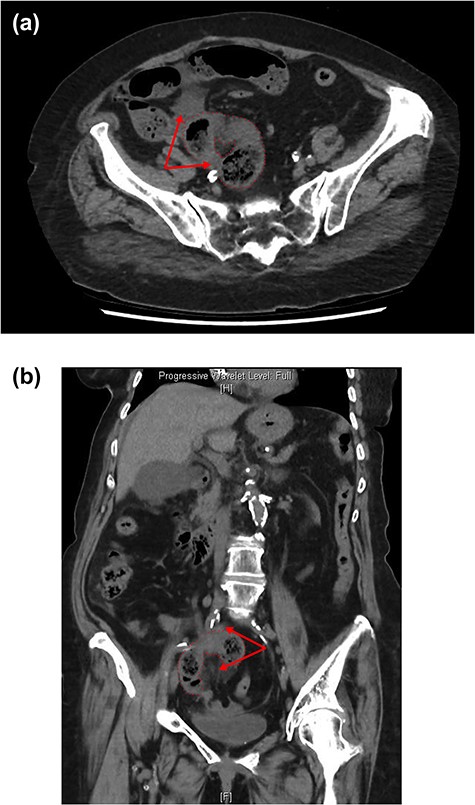

An abdominal examination revealed a focal tenderness over her right lower quadrant and right pelvis and generalised abdominal distention. Computed tomography (CT) scan (Fig. 1a and b) showed small bowel faecalisation in the distal small bowel with a focal bowel loop in the right iliac fossa displaying engorgement of its mesentery with moderate volume of free fluid in the right paracolic gutter and Morison’s pouch. Findings were highly suspicious for a closed loop bowel obstruction with bowel wall compromise.

CT axial (a) and coronal (b) views showing loop of strangulated small bowel with surrounding fat stranding and free fluid (red arrows).